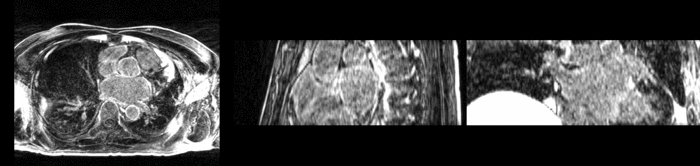

Top) Pre-ablation. Bottom) Post-ablation.

The pre and post-ablation images are shown below. The data dimensions are 320x320x20 for the pre-ablation, and 288x288x20 for the post-ablation. We observe differences in shape present due to respiration and subject placement. Furthermore, the ablation procedure has scarred the tissue of the atrium, which can be seen in bright white in the post-ablation image. As a result, the shape of the atrium has likely changed. For these reasons, this registration task is particularly challenging. The alignment before registration is shown below.

Alignment before registration. Pre-ablation in gray, post-ablation in red.